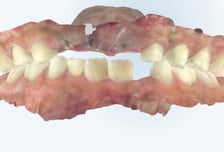

"와자작" 부럼 깨다 우리 아이 유치 '쏙'…"영구치 나잖아" 방심했다간

오늘(12일)은 우리 민족이 오랜 세월 이어온 전통 명절인 정월대보름이다. 이맘때면 가족과 이웃이 모여 견과류 등 단단한 음식을 깨물어 먹으며 한 해의 건강과 행운을 기원하는 '부럼 깨기' 풍습이 자연스레 떠오른다. 농경 사회에서 시작된 이 전통은 오늘날에도 많은 이들의 마음속에 자리 잡고 있으며, 특히 새 학년을 준비하며 방학 동안 심심해할 수 있는 우리 아이들에도 재미있는 풍습이기도 하다. 하지만 견과류를 비롯한 단단한 음식은 어린아이들의 치아 건강에 해를 끼칠 수 있어 주의해야 한다. 가톨릭대 서울성모병원 치과 한성훈 교수는 "성장기 아이들의 유치는 영구치보다 법랑질이 얇아 쉽게 손상될 수 있어, 무리한 힘을 가하면 치아에 금이 가거나 깨질 위험이 있다"며 "이는 심한 통증을 유발하거나, 영구치 맹출에 영향을 줄 수 있다"고 경고했다. 만약 유치가 조기에 빠진다면 아래에서 자라는 영구치의 맹출 공간이 부족해져 치열이 어긋날 가능성이 커진다. 질병관리청 국가건강정보포털에 따르면,